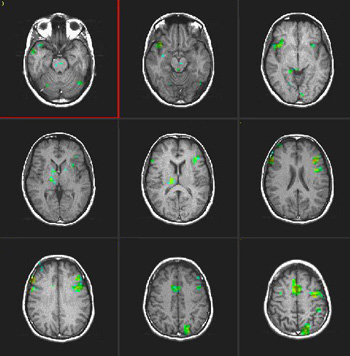

Studies in Late Bilinguals

Right handed 34 year-old-woman. Native language: Spanish

Type: Verbal fluency task

ON: Retrieve verbs related to presented nouns

OFF Spell given words |

| T-Test |

0.0001 |

3.8 |

| Images |

Spanish

English

There is activation of Broca's area in both languages. The right thalamic activation is noted only in the second language. There is also greater activation of the right inferior frontal gyrus in the second language than in the mother language. SMA is more pronounced on the right in both languages. |